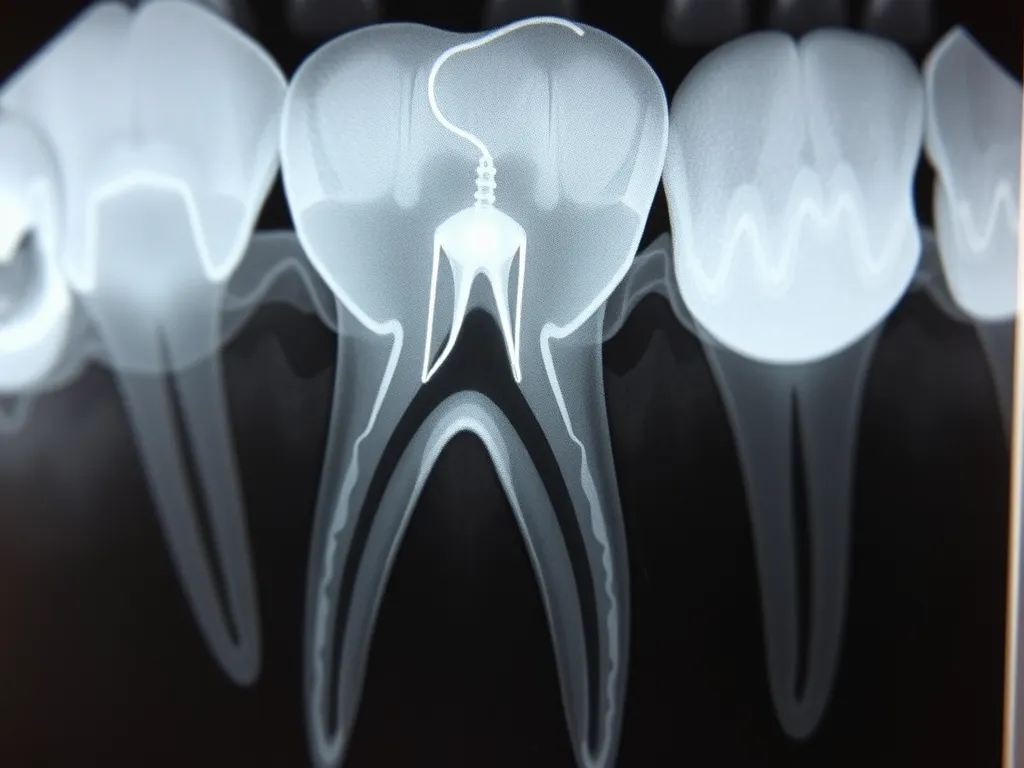

Inną przyczyną może być niewłaściwa ocena sytuacji przed zabiegiem. Brak zdjęcia RTG przed ekstrakcją utrudnia precyzyjne określenie przebiegu i długości korzeni, co zwiększa ryzyko ich pozostawienia. Czasami decyzja o nieusunięciu fragmentu korzenia wynika z obawy przed uszkodzeniem sąsiednich struktur anatomicznych, np. nerwów czy zatoki szczękowej.

Usunięcie pozostawionego korzenia jest konieczne w większości przypadków, zwłaszcza jeżeli występują objawy bólu, obrzęku lub tkliwości dziąsła. Leczenie stomatologiczne powinno być niezwłocznie podjęte, gdy na zdjęciu RTG widoczne są patologiczne zmiany wokół korzenia – np. torbiele lub powikłania okołowierzchołkowe.

Zabieg usunięcia korzenia zęba wykonywany jest najczęściej w znieczuleniu miejscowym, co zapewnia komfort i minimalizuje ból podczas procedury. Przed rozpoczęciem zabiegu lekarz zleca zdjęcie RTG, aby dokładnie ocenić położenie i długość pozostawionego fragmentu. Następnie, przy użyciu specjalistycznych narzędzi, chirurg stomatologiczny oddziela korzeń od otaczających tkanek i usuwa go z zębodołu.

Istnieje kilka wyraźnych wskazań do usunięcia korzenia zęba, które powinny być respektowane przez każdego stomatologa. Przede wszystkim są to przewlekły stan zapalny, widoczne na RTG zmiany okołowierzchołkowe, obecność torbieli oraz powracające infekcje dziąseł. Należy również rozważyć zabieg w przypadku utrudnionej rehabilitacji protetycznej.

• Wskazania do usunięcia korzenia obejmują przewlekły stan zapalny, zmiany okołowierzchołkowe widoczne na RTG, przetoki ropne oraz utrzymujący się ból lub obrzęk.